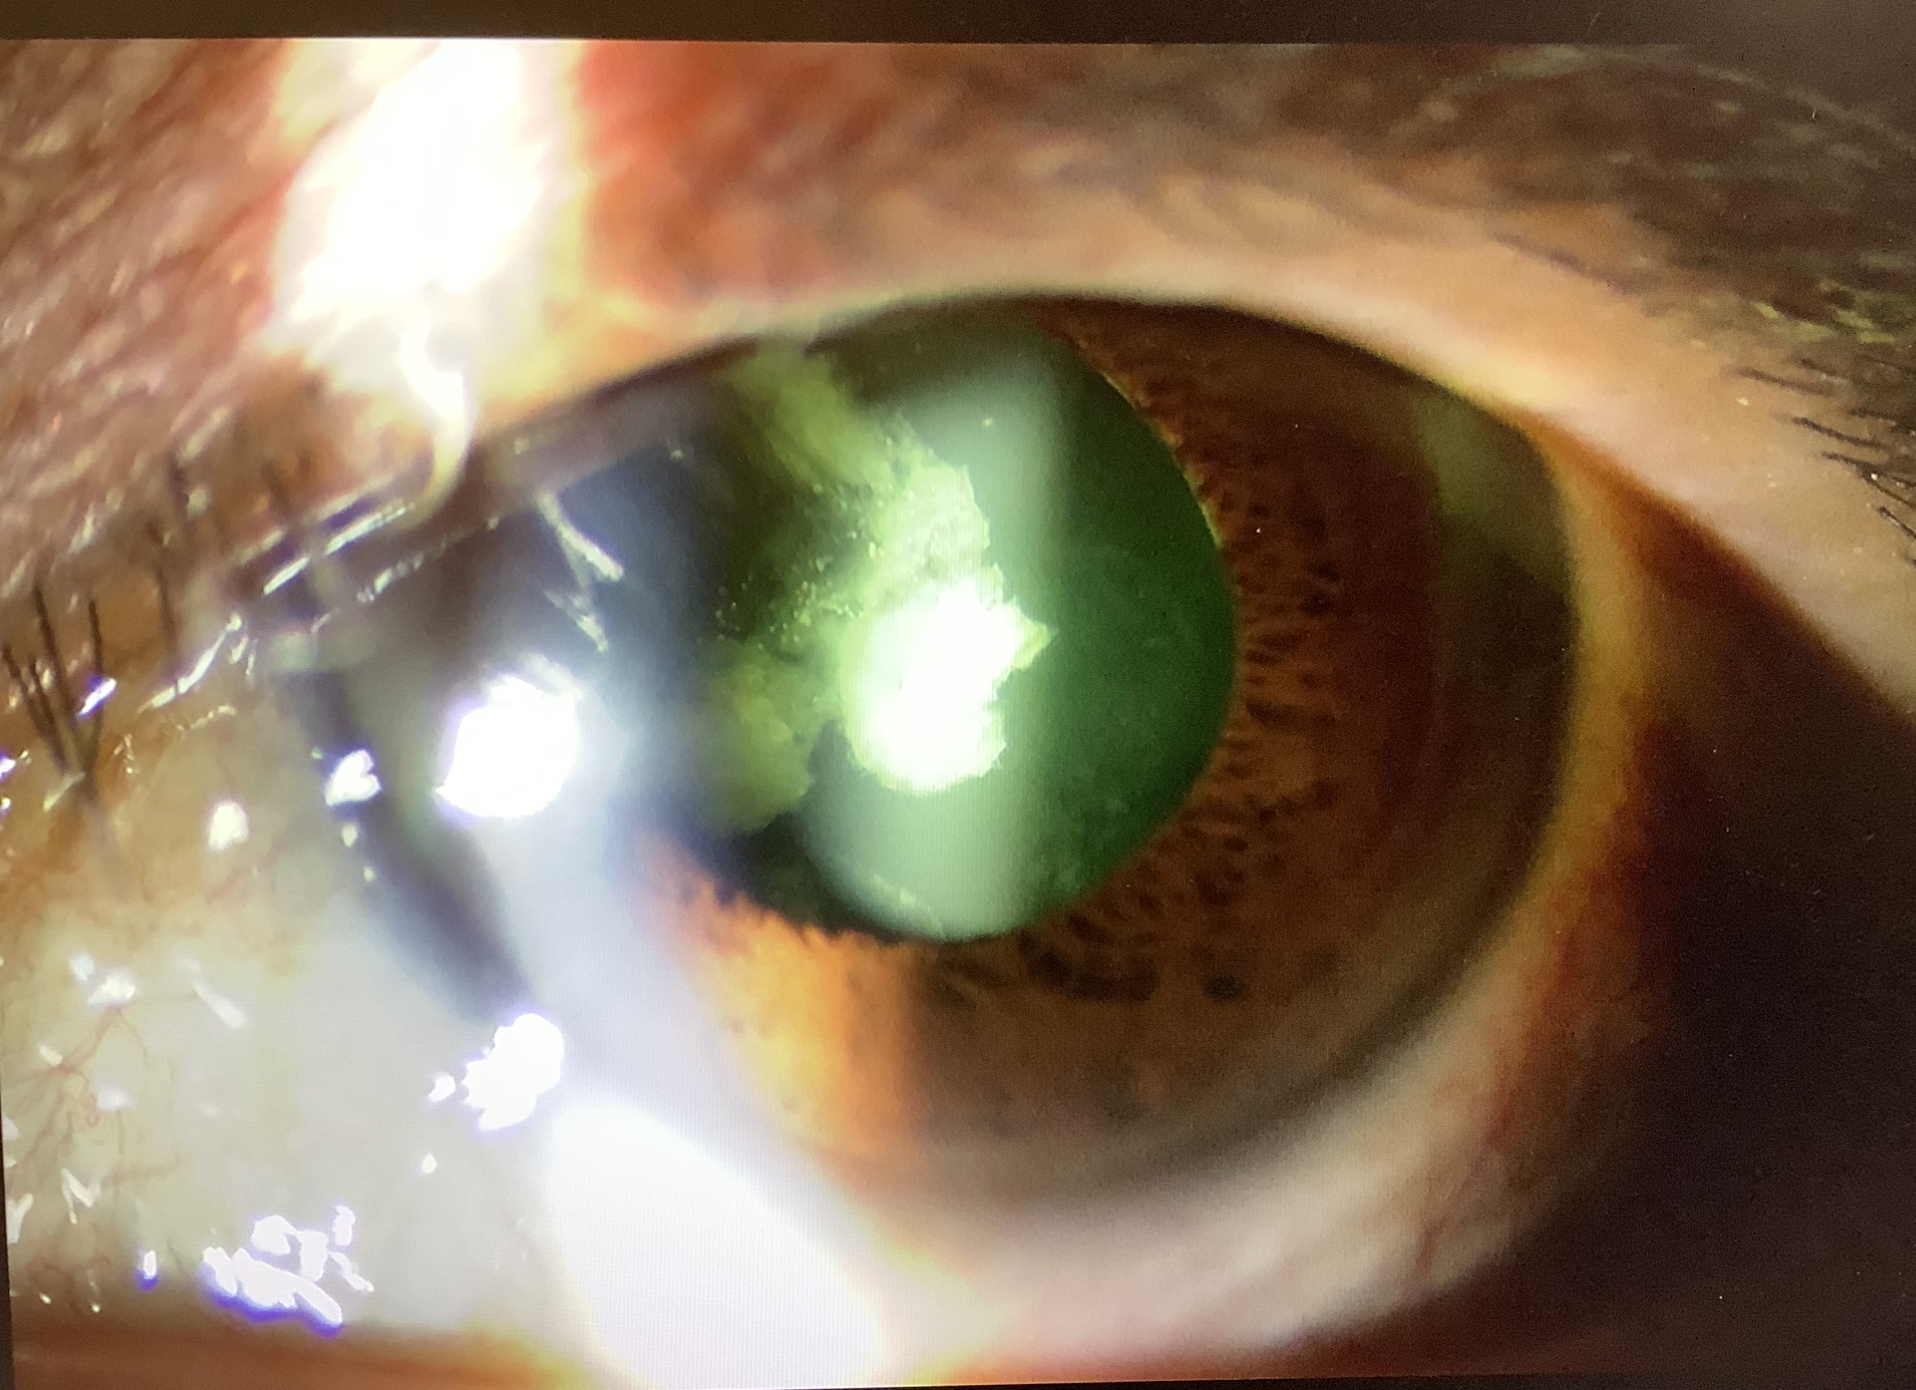

今日、外来を受診された50代後半の女性の方は、10年くらい前に他院で多焦点レンズを使った白内障手術を受け、1年くらい前から左眼が見えにくくなり、また違う医院を受診したところ、後発白内障と眼内レンズの濁りを指摘され、レンズの入れ換えを提案され、当院に相談にいらっしゃいました。

眼内レンズはAlcon社のReSTOR(レストア)という2焦点レンズが入っていました。このレストアの元となるAcrySof(アクリソフ)というレンズは、手術で眼の中に入れた後、しばらくしてレンズの表面や内部に水泡が現れることで、“表面散乱”や“グリスニング”と呼ばれるレンズの混濁を生じるとされています。以前、他のメーカーの眼内レンズでカルシウムの沈着により視機能、つまり見え方に影響を及ぼしてしまうレンズが問題になったことはありましたが、このアクリソフの濁りは視機能には影響しないとされており、基本的にレンズの入れ換えをする必要はありません。

それから、この患者さんはご自分の眼の写真を見せてもらった時に『レンズが黄色く濁っていて心配になった』ともおっしゃっていましたが、このレストアもそうですが、日本で使われているレンズは着色レンズが多く、黄色のレンズが一般的なので、レンズが黄色いことは全く心配しなくて大丈夫です(この方が見え方が自然といわれています)。